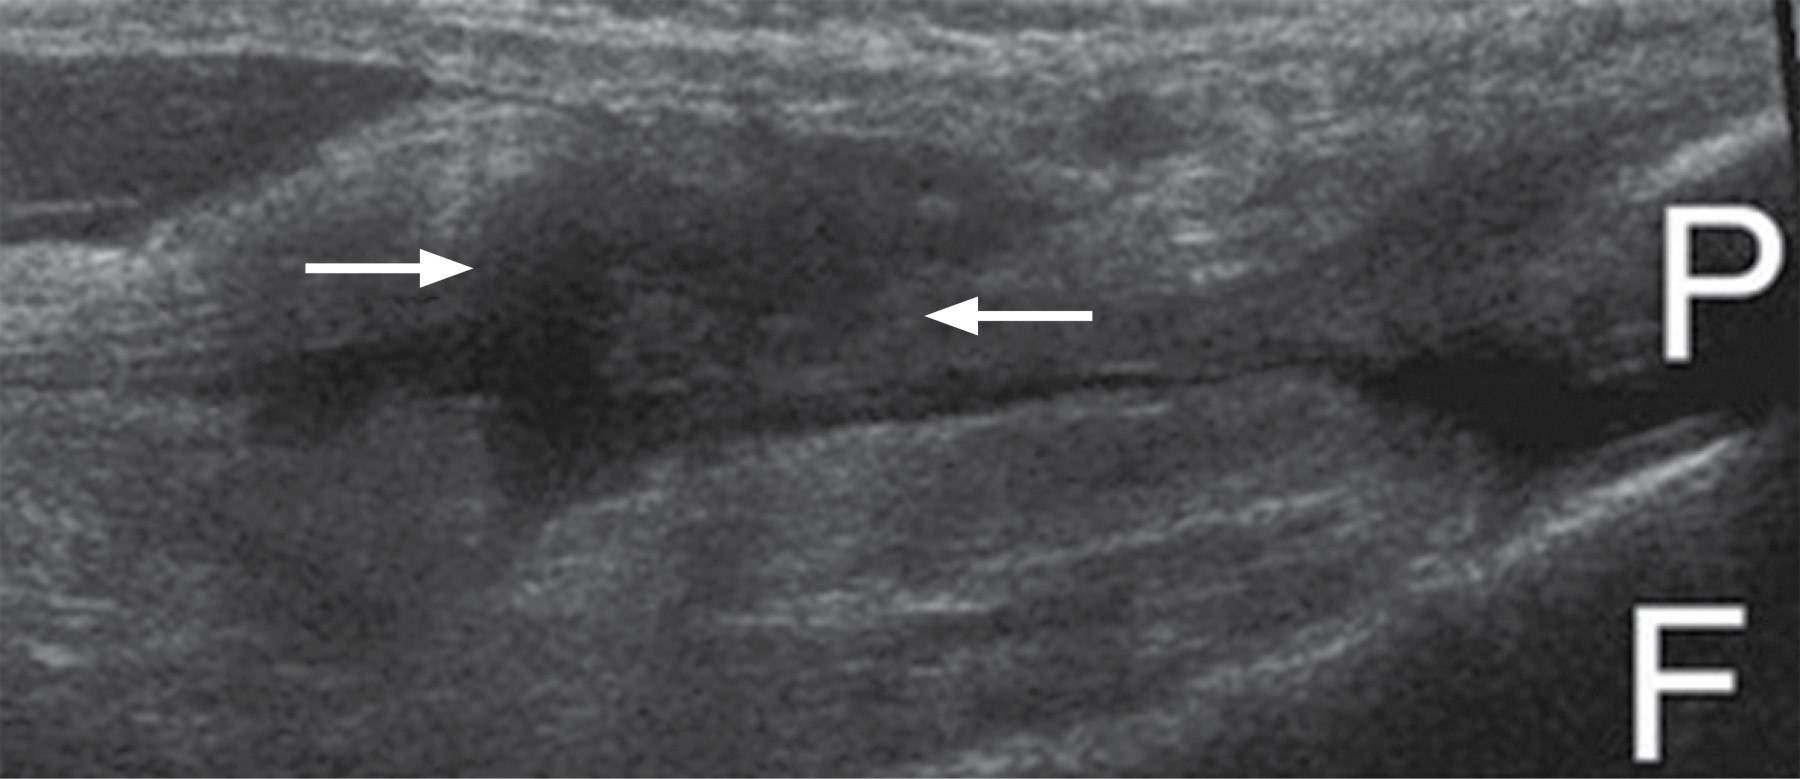

Masculino de 45 años sufre traumatismo directo en tercio distal de la cara anterior del muslo izquierdo, valorado por médico ortopedista quien observó aumento de volumen acompañado de edema prepatelar, doloroso a la palpación, depresión a la palpación en la topografía del tendón del cuádriceps, dolor a la flexión pasiva y activa. El ultrasonido muestra pérdida del patrón fibrilar e interrupción de la mayor parte de las fibras del tendón del cuádriceps (Figura 1); en forma complementaria se decide solicitar estudio de resonancia magnética de rodilla donde existe ruptura completa del tendón del cuádriceps en su inserción y como signo indirecto, situación de rótula baja (Figuras 2 A-C). Las lesiones del cuádriceps tienden a ser comunes entre atletas y adultos activos, desde contusiones musculares leves hasta la ruptura completa del tendón. El cuádriceps se compone del recto femoral, vasto lateral, vasto medial y vasto intermedio; éstos se insertan en la rótula como el tendón del cuádriceps común. El tendón envuelve la rótula y se inserta en la tuberosidad tibial.1 La localización de la ruptura se demuestra que está a 1-2 cm de la parte superior del polo rotuliano , en la mayoría de los casos en la región avascular del tendón.2 La edad de presentación ocurre en adultos mayores de 50 años o atletas más jóvenes.3,4 El paciente puede experimentar sensación de desgarro en la rótula o "explosión" seguida de aumento de volumen y dificultad para soportar el peso.5 Es posible desarrollar hemartrosis aguda y sensibilidad focal por encima de la rótula, no se puede mantener la pierna recta ni levantar la pierna contra la gravedad mientras está en decúbito supino.4,6 Los hallazgos por imagen y las radiografías revelan fracturas por avulsión y rótula baja (medición Insall-Salvati), por ultrasonido se observa zona hipoecoica o anecoica, incremento en el grosor o disminución de la ecogenicidad.7 La resonancia magnética (mejor método) demuestra interrupción de la mayor parte de las fibras del tendón, como signo secundario el tendón rotuliano adquiere aspecto ondulado debido a la falta de tensión en extensión,4 también se demuestra derrame articular, edema de la medular ósea en la porción más superior de la rótula o edema intramuscular.4,5

Figura 2